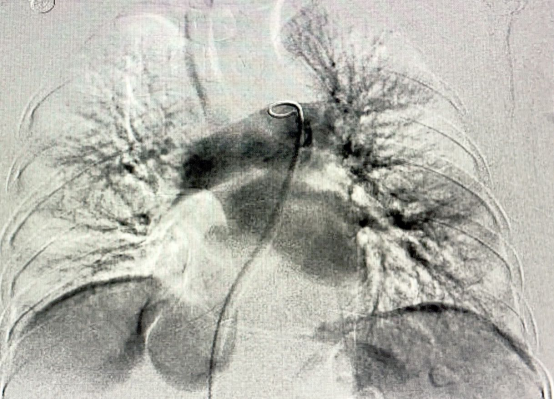

取得患者及家属同意后,经过缜密的术前准备,11月6日,在影像中心、介入导管室等多学科密切配合下,张勇带领施益忠、吴浩、祝大明手术团队,成功为患者实施了微创介入手术,手术共用时约90分钟。术中造影见左上肺动脉开口及右侧肺动脉主干巨大血栓影,管腔血流完全堵死。予以血栓机械碎栓+药物靶向溶栓术后,肺动脉血流完全恢复,患者憋闷症状明显好转,术后患者恢复良好,1天后可下床自由活动。日前患者已康复出院,转居家抗凝治疗及门诊随访。